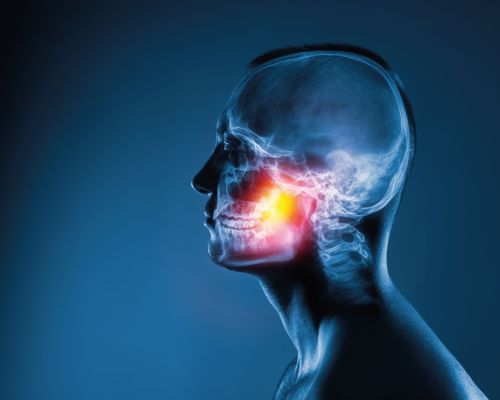

Mikrovaskulárna dekompresia trojklanného nervu na ružinovskej neurochirurgickej klinike

Na Neurochirurgickej klinike SZU a UNB Ružinov sa kolektív lekárov pod vedením prednostu kliniky MUDr. Milana Lišku, PhD, MPH a zástupcu kliniky MUDr…